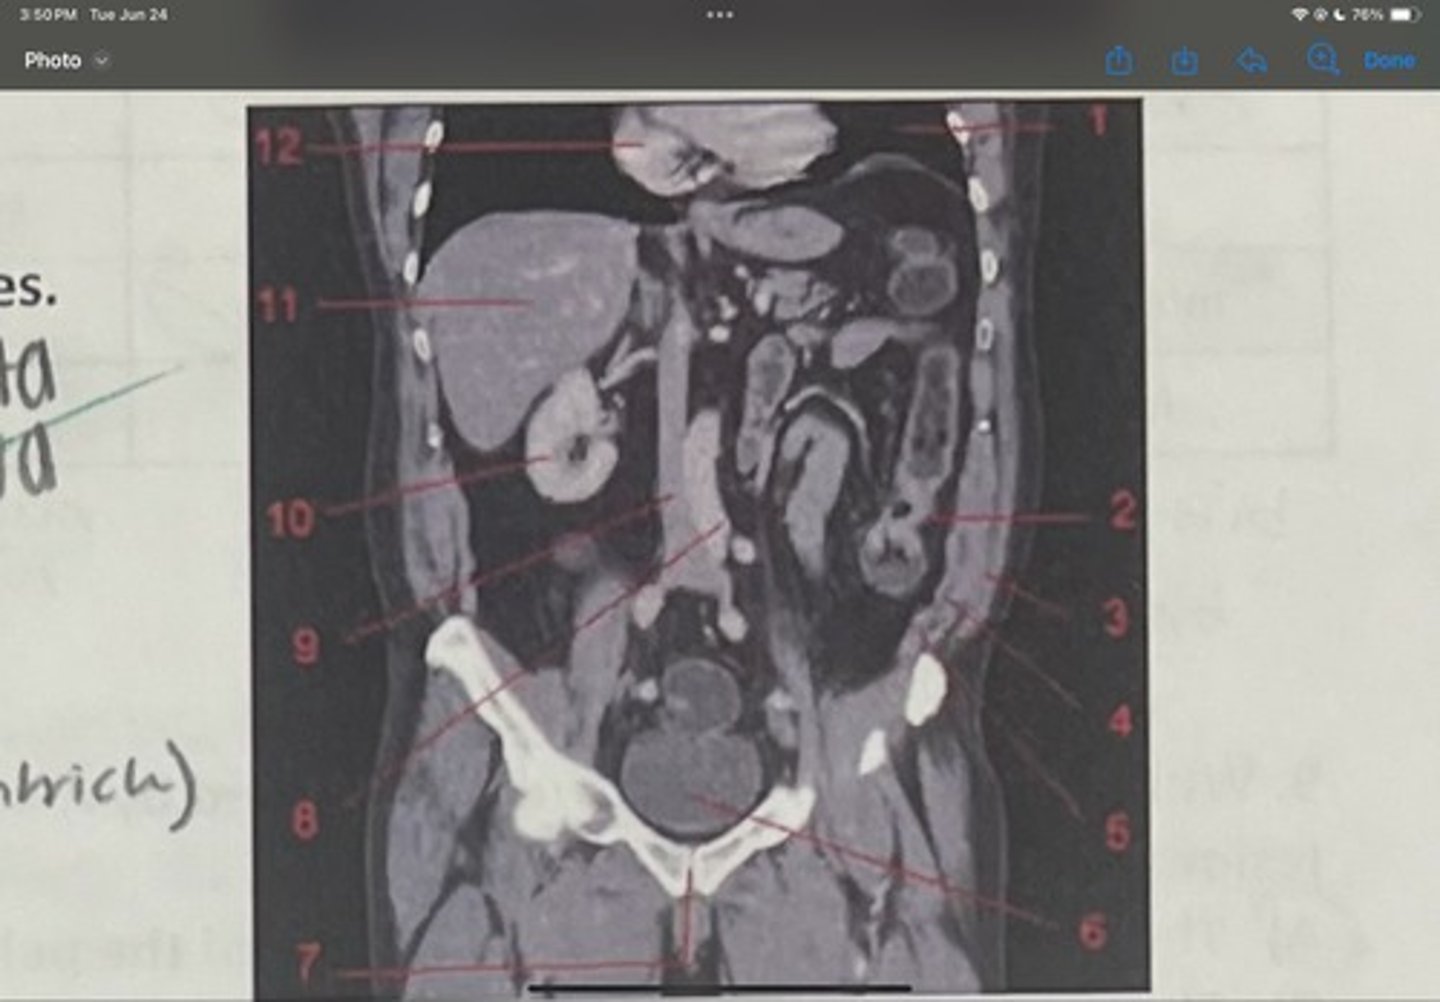

What is 1

Descending colon

What is 2

External oblique

What is 3

Internal obliques

What is 4

Transversus abdominis

What is 5

Bladder

What is 6

Pubic sysmphysis

What is 7

Abdominal aorta

What is 8

Inferior vena cava

What is 9

Right kidney

What is 10

Liver

What is 11

Heart (right ventricle)

What is 12

Subcostal nerve (T12)